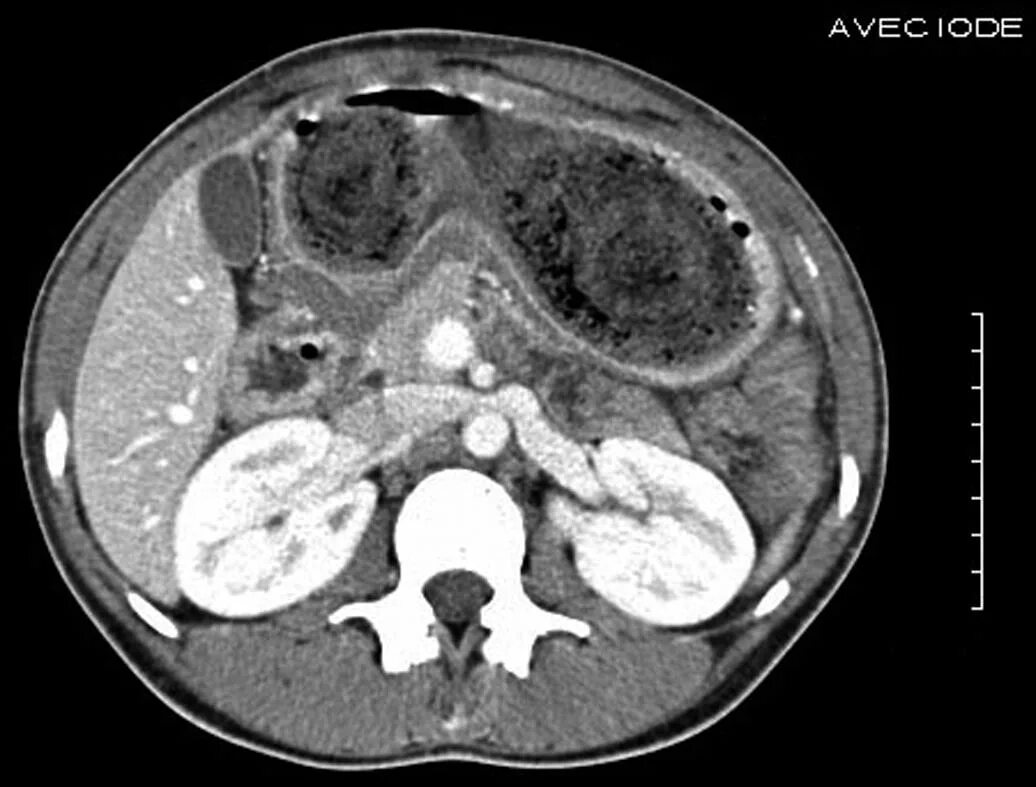

Язва желудка кт